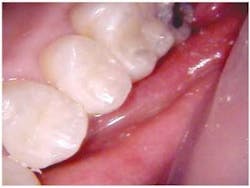

Early inter-proximal decay #12 (DIFOTI and X-ray)

Peers, et al in 1993 found that the sensitivity of fiber-optic transillumination in the discovery of dental caries exceeded that of radiographs. Early phases of tooth decay are currently difficult to detect. While radiographs can disclose established cavities, particularly those that occur between the teeth, they are not effective in detecting early decay. Vaarkamp and Veerdonschot demonstrated that early diagnosis of approximal carious lesions was feasible when light was propagated through the carious tissue.

Schneiderman, et. al. (Caries Research 1997) demonstrated that DIFOTI is two times more sensitive than bitewing radiographs for detection of interproximal tooth decay (X-ray 31 percent; DIFOTI 69 percent); four times more sensitive for occlusal decay (X-ray 20 percent; DIFOTI 80 percent); and 10 times more sensitive for smooth surface decay (X-ray 4 percent; DIFOTI 41 percent).